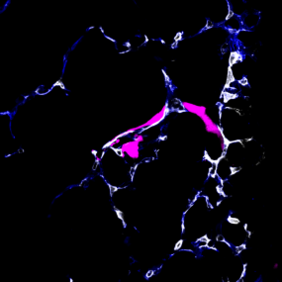

Um sich im Körper zu verbreiten, nutzen Krebszellen die Blut- oder Lymphbahnen. Wissenschaftler im DKFZ und in der Universität Heidelberg haben nun ein Verfahren entwickelt, um bei Mäusen das Verhalten wandernder Krebszellen unmittelbar bei Ankunft im metastatischen Organ – in diesem Fall der Lunge – zu beobachten.

Dabei entdeckte das Team um die beiden Erstautoren Moritz Jakab und Ki Hong Lee, dass manche Tumorzellen, sobald sie im Zielorgan angekommen sind, aus dem Blutgefäß austreten und in einen Ruhezustand fallen. Andere Krebszellen dagegen fangen direkt im Blutgefäß an, sich zu teilen und zur Metastase auszuwachsen.

Diese Entscheidung wird von den Endothelzellen gesteuert, die alle Blutgefäße von innen auskleiden. Sie schütten Faktoren des Wnt-Signalwegs aus, die den Austritt der Tumorzellen aus dem Blutgefäß fördern und damit den Ruhezustand einleiten. Schalteten die Forscher die Wnt-Faktoren aus, kam es nicht mehr zur Latenz.